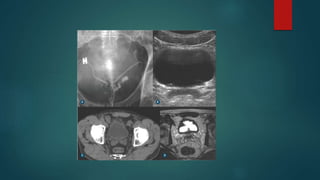

CISTO CONGÊNITO

 Geralmente um achado incidental

 Em 60% dos casos associado a agenesia renal ipsilateral

 Ocorre bilateralmente em 44-60-% dos pacientes com doença

renal policística autossômica dominante.

CISTO UTRICULAR